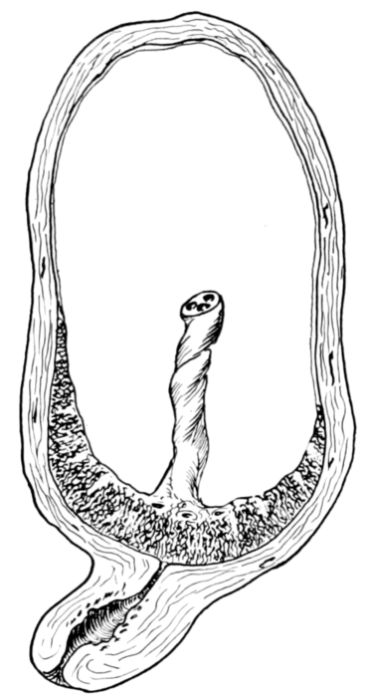

| 20. | Diagram of developing fetus, cord, membranes and placenta in utero | 69 |

| 25. | Embryo about 5.5 cm. long in amniotic sac | 77 |

| 26. | Outlines of fetus at different stages | 78 |

| 27. | Full term fetus in utero | 81 |